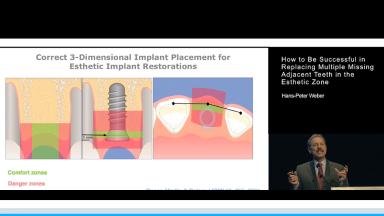

Replacing multiple missing teeth in the esthetic one is considered a complex treatment. Clinicians need to be well aware of potential pitfalls on the road to successful treatment outcomes, notably in the presence of advanced or complex indications for implant treatment, one example being indications with missing adjacent teeth in the anterior maxilla.

By identifying the risks and addressing them appropriately during the diagnostic and treatment planning phase, numerous esthetic short- or longterm complications may be avoided. It is considerably easier to prevent complications than to treat them.

- recognize general and esthetic modifiers that may influence treatment outcomes

- describe treatment protocols that reduce the risk for complications